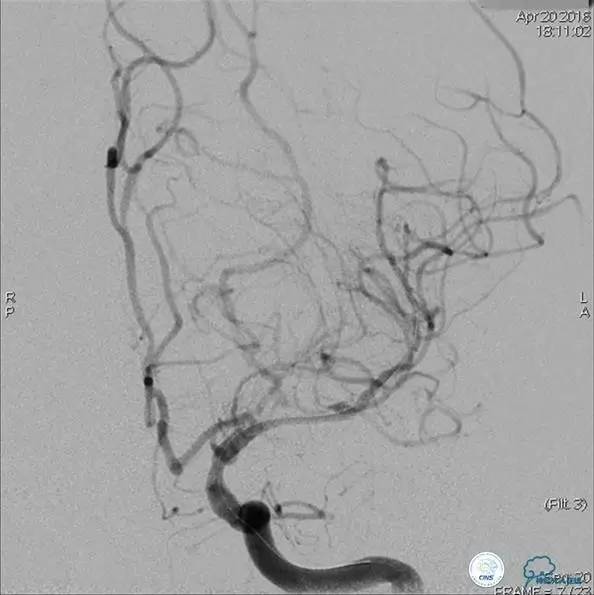

患者:58岁男性,反复头晕、肢体无力3月,当地造影见多发颅内动脉狭窄、闭塞,转来我院。

▼首先行颈动脉CTO开通术,手术顺利,Wallstent支架。

▼1周后行右侧椎动脉V4段CTO开通术。

▼微导丝穿过狭窄段,微导管造影,小球囊预扩张,2mm。

▼根据血管情况选择较大球囊再次预扩张。

▼置入2枚Wingspan支架,手术成功。

▼术后即刻CT,梗死灶内再灌注出血。

患者无症状,中性治疗。4月21日电话随访,一般情况好,当地CT示出血吸收期。